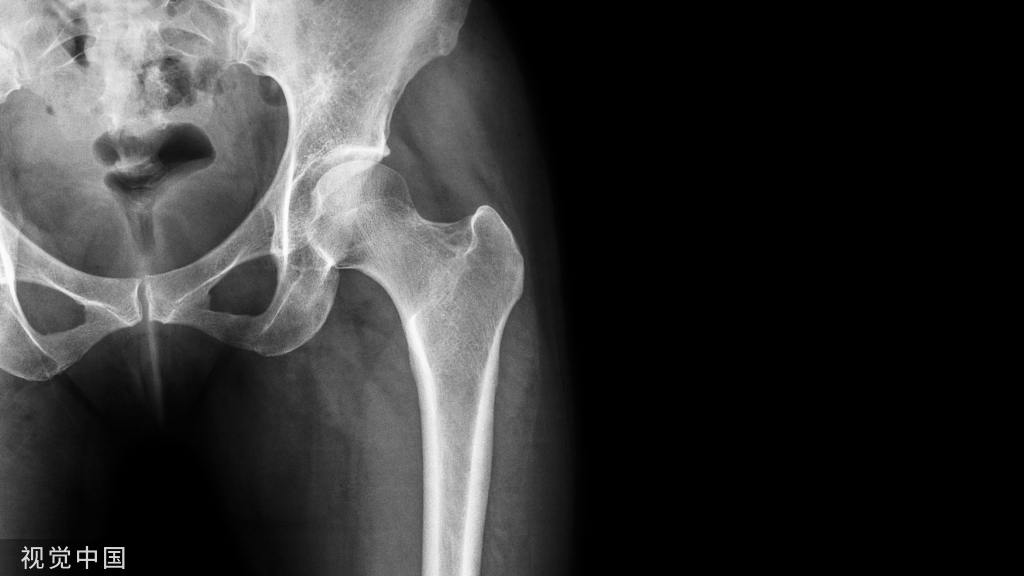

【骨科小技巧】髋关节复位后的固定、功能锻炼技巧!

髋关节复位后的固定、功能锻炼技巧!

复位后并不意味着治疗已经结束了,复位后的固定以及功能锻炼非常关键,复位后用抬腿垫将髋关节固定于轻度外展位,复位后六周内禁止髋关节内旋、内收、髋关节屈曲大于90°。